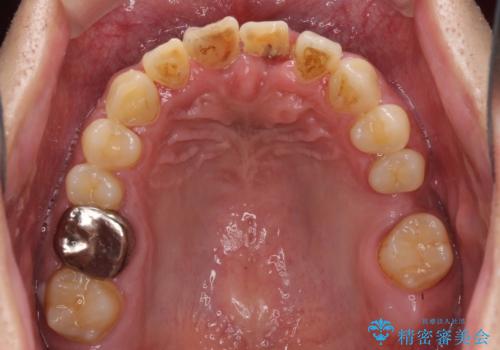

- ソーシャルメディアでのゲームに夢中になっている最中に車と接触し、前歯の抜歯を余儀なくされた患者様です。

初診時では前歯が保存できる可能性も模索しましたが、損傷が激しく3歯を抜去することとなりました。

保存となった隣在歯も神経が失活していており、補綴治療が必要であったので、オールセラミッククラウンにて補綴治療することとしました。

奥歯には元々欠損があり、欠損に伴う咬合不正も認められたため、部分矯正を行った上でインプラント補綴治療も行うこととしました。